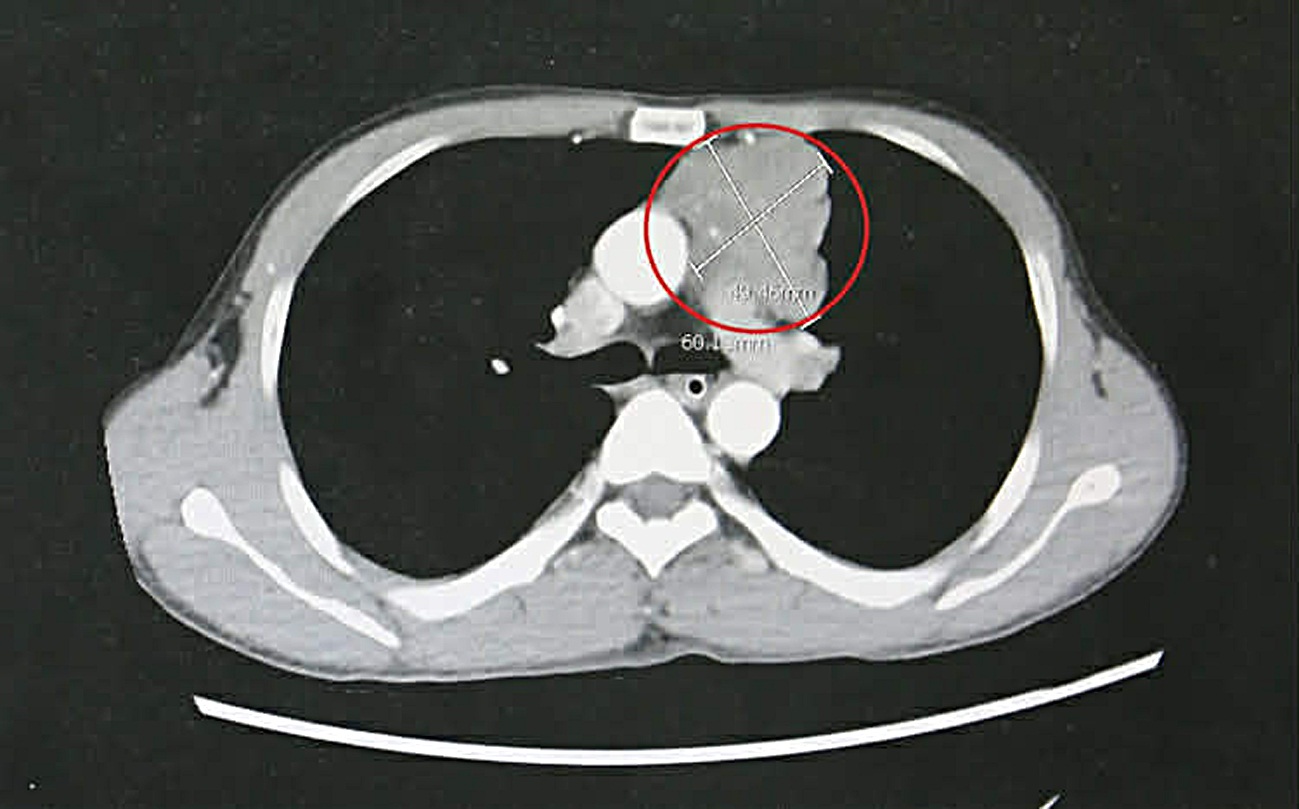

Qua thăm khám lâm sàng, cơ lực chi chỉ còn 3/5, phản xạ kém, cơ lực cổ yếu, cơ hô hấp suy giảm. Kết quả chụp cắt lớp vi tính lồng ngực phát hiện khối u trung thất trước kích thước lớn khoảng 4 x 6cm, xâm lấn thần kinh hoành, bên trong có vôi hóa.

Bệnh nhân được chẩn đoán nhược cơ nặng do khối u tuyến ức và chỉ định phẫu thuật cắt toàn bộ tuyến ức giúp loại bỏ nguyên nhân gây nhược cơ.

Khối u tuyến ức kích thước lớn của bệnh nhân gây nhược cơ - Ảnh BVCC